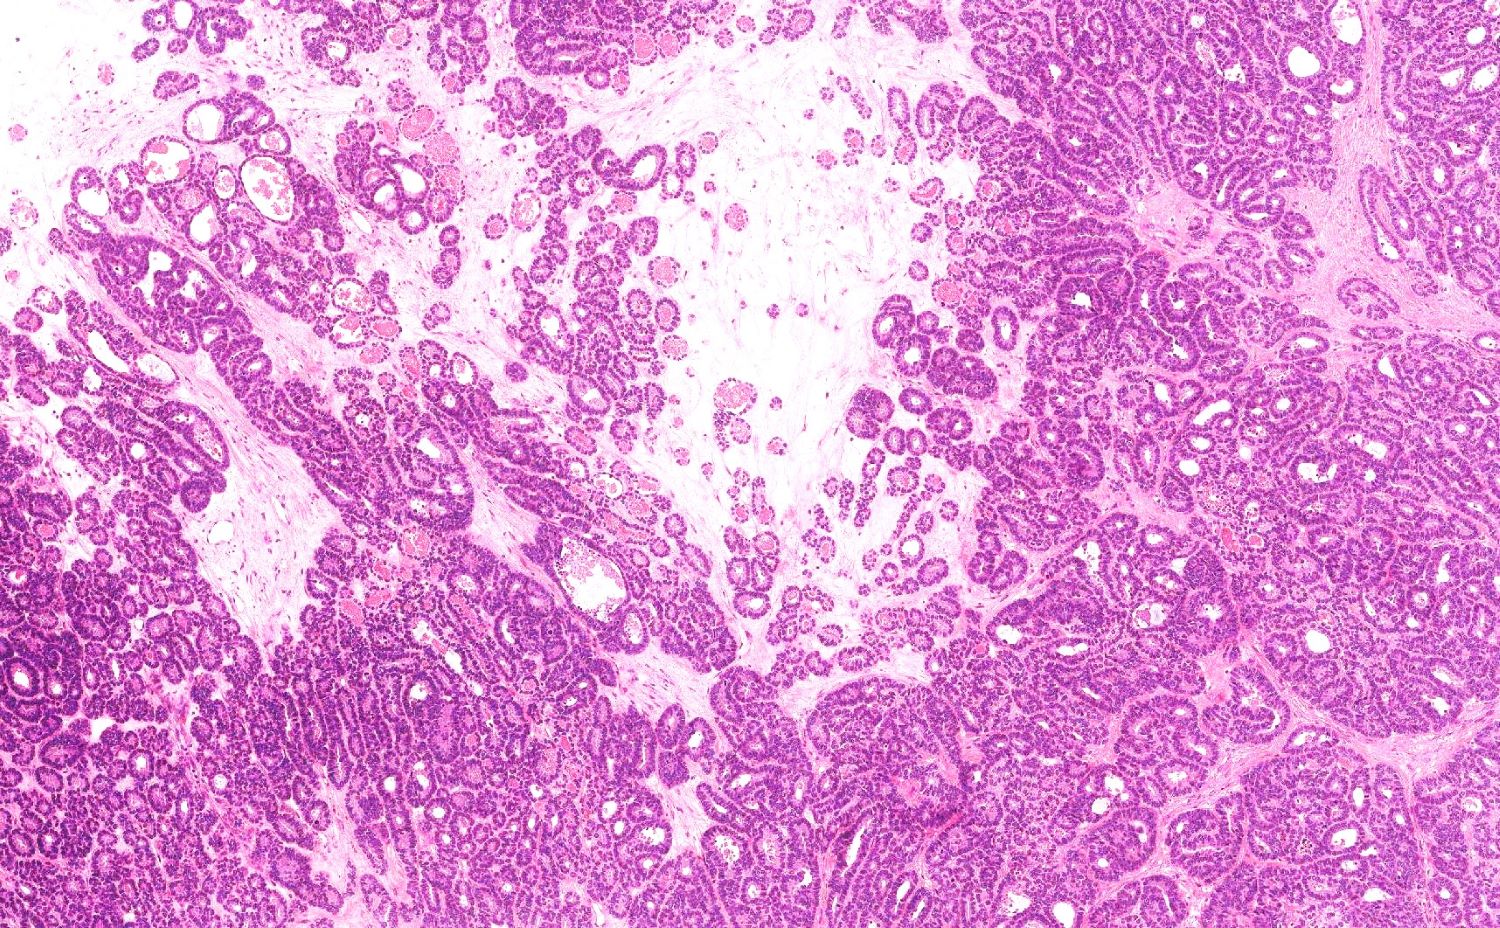

- Variety of histologic patterns that may be present within the same tumor

- Most frequently small tubules with ductal / glandular growth

- Papillary, solid growth, trabecular, retiform, sex cord-like, sieve-like, glomeruloid and spindle cell areas have all been described

- Luminal eosinophilic secretions are characteristic but not always identified

- Tumor cells can be flattened, cuboidal or columnar with mild to moderate cytological atypia

- Clear cell features can be seen but are less common

- High grade cytological atypia is usually not a predominant feature

- Nuclei show vesicular chromatin and nuclear grooves

- Sarcomatoid transformation has been seen in rare instances

- Squamous, ciliated or mucinous differentiation (metaplasia) are not present and there are no associated mesonephric remnants (J Clin Med 2021;10:698)

Microscopic (histologic) images

Contributed by Daniel Graham, M.D., Adele Wong, M.B., B.Ch., B.A.O. and Lucy Ma, M.D.